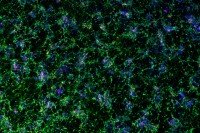

In the Lab

Stem Cell Research Identifies Potential Drugs for Treating Zika Infection

Researchers from MSK and Weill Cornell have found that two compounds appear to fight off infection with the Zika virus.